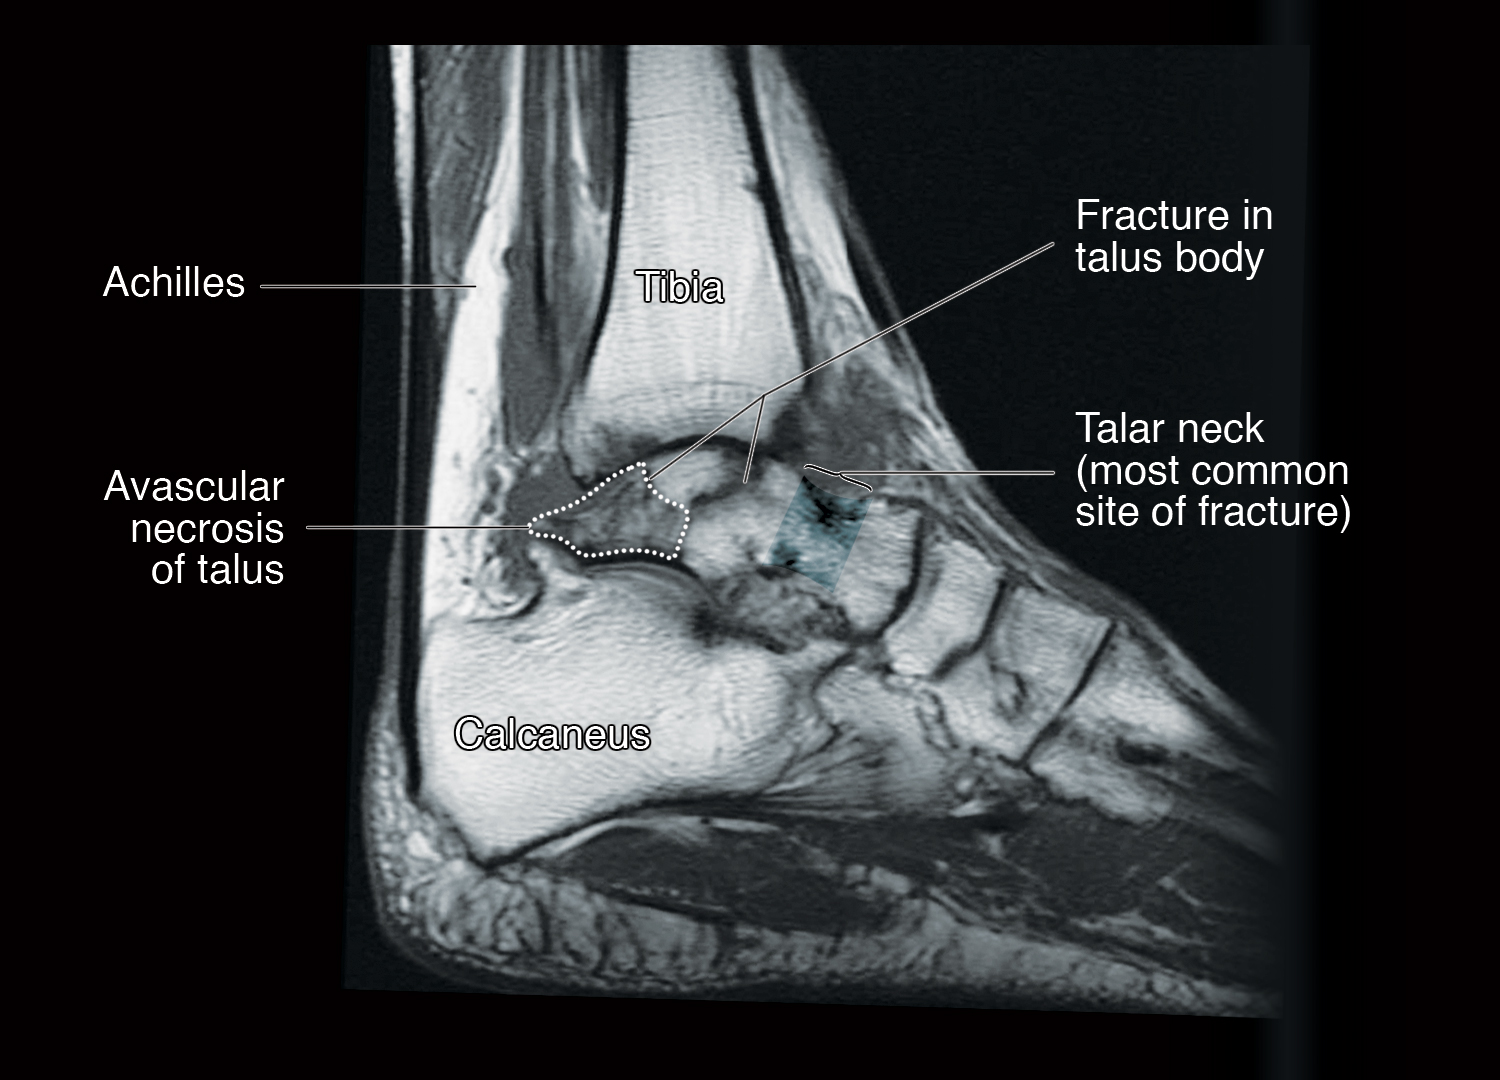

Figure 4 from Avascular Necrosis of the Foot and Ankle Semantic Scholar What Is Avascular Necrosis Of The Ankle Although avascular necrosis of the talus is relatively uncommon compared to other joints like the hip or. What is talar avascular necrosis? Avascular necrosis of the talus happens when the talus bone, the bone in the center of your ankle, loses some of its blood supply and is no longer. Avascular necrosis is a condition that causes bone tissue to. What Is Avascular Necrosis Of The Ankle.